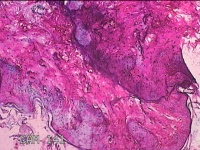

左侧腋下结节

性别

女

年龄

46岁

临床诊断

皮下结节

一般病史

发现左侧腋下一结节1周,伴局部隐痛不适,无发热。

标本名称

大体所见

灰白暗红色组织1.8x1.3x0.3cm一块,表面带梭形皮肤1.8x0.5cm,皮下见结节1.2x0.8cm,切开结节呈实性,切面灰白淡黄色,质软。

炎症性病变。